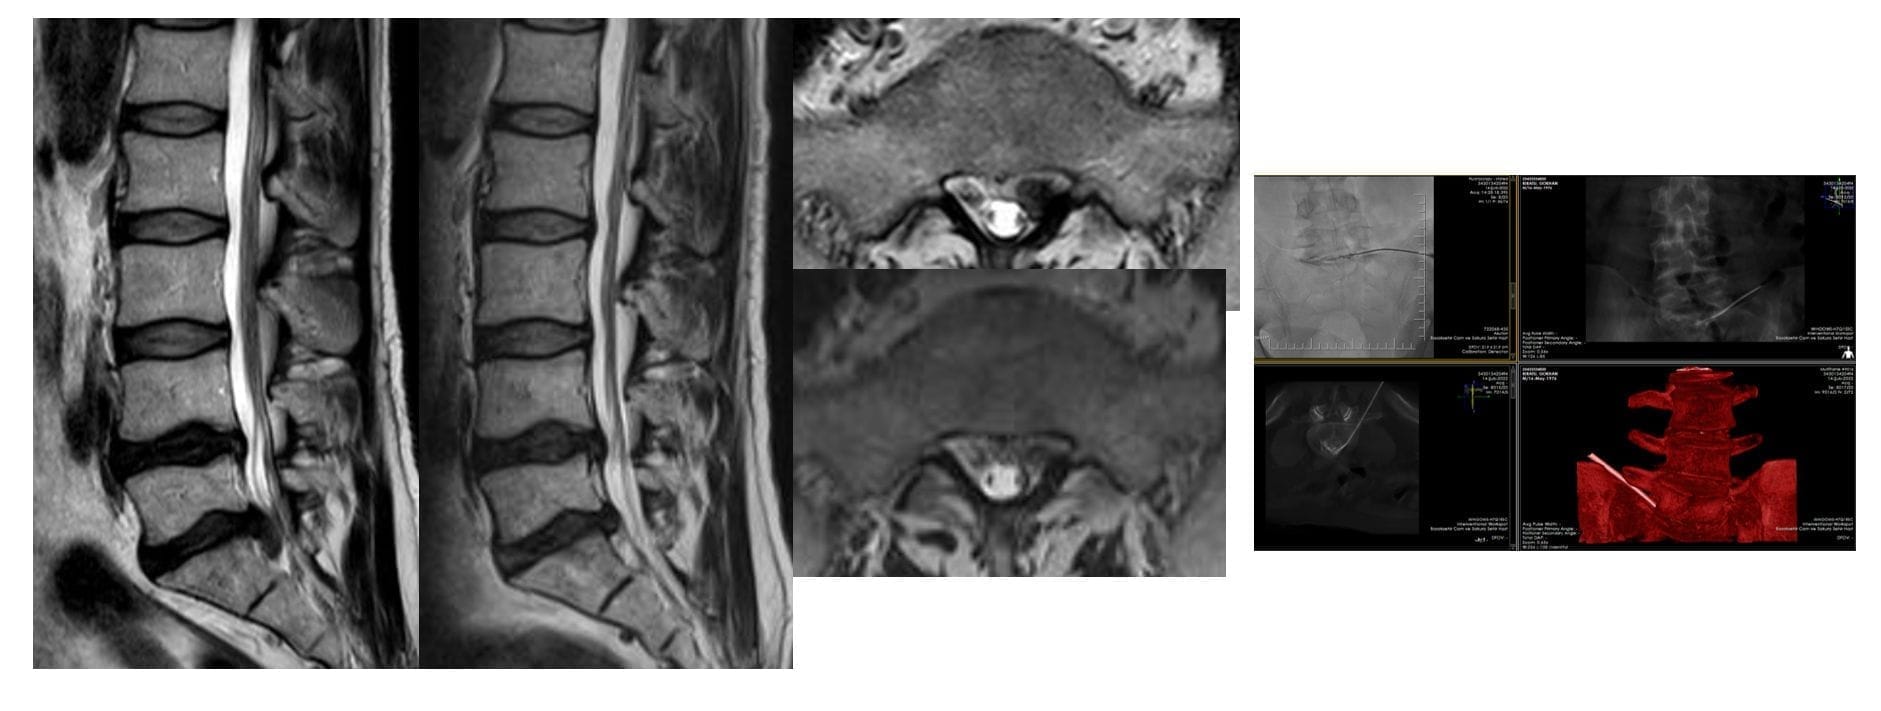

Laserbehandlung zur Bandscheibenverkleinerung:

Bei dieser Methode wird die Nadel ähnlich wie bei der Radiofrequenz in die Bandscheibe eingeführt, und durch die Nadel wird eine Laserfaser geführt, die Wärme überwacht und eine bestimmte Energiemenge in die Bandscheibe einbringt, um die Bandscheibe langfristig zu verkleinern.

- Laser-Diskektomie: Mit einer Lasernadel wird Wärmeenergie in die Bandscheibe eingebracht, um eine Schrumpfung der Bandscheibe zu erzielen.